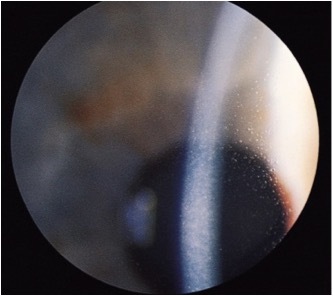

what are the 4 different presentations for cogan microcystic dystrophy?

dots, microcysts, fingerprints (least common) and maps (most common)